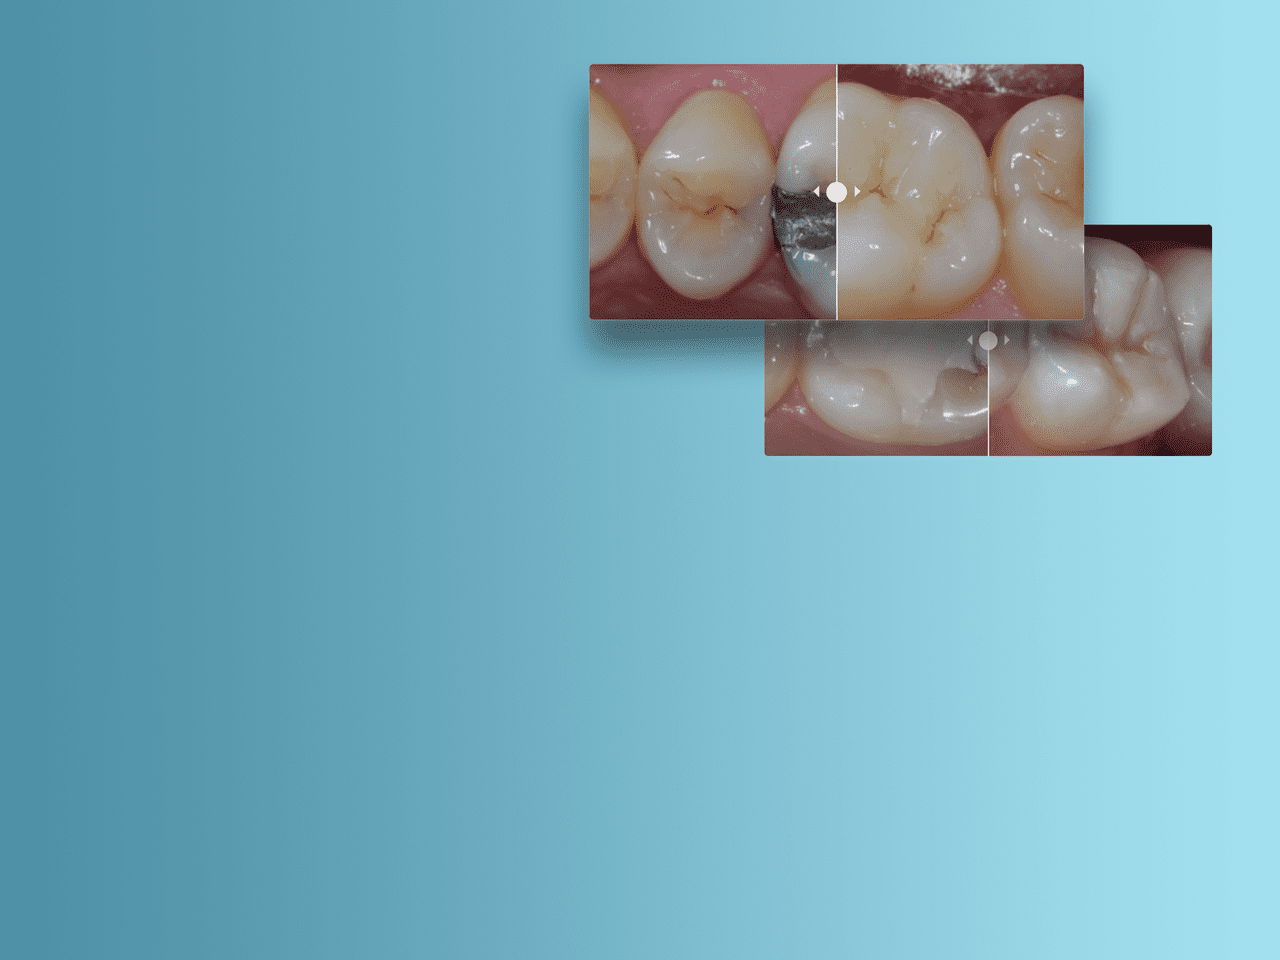

Image:

Before - Posterior Restoration using A2 shade of Spectra ST restorative composite (Source: Dr. A. Ferrando)

After - Amalgam Replacement with Advanced Layering Technique using A2 and Bleach White shade of Spectra ST restorative composite